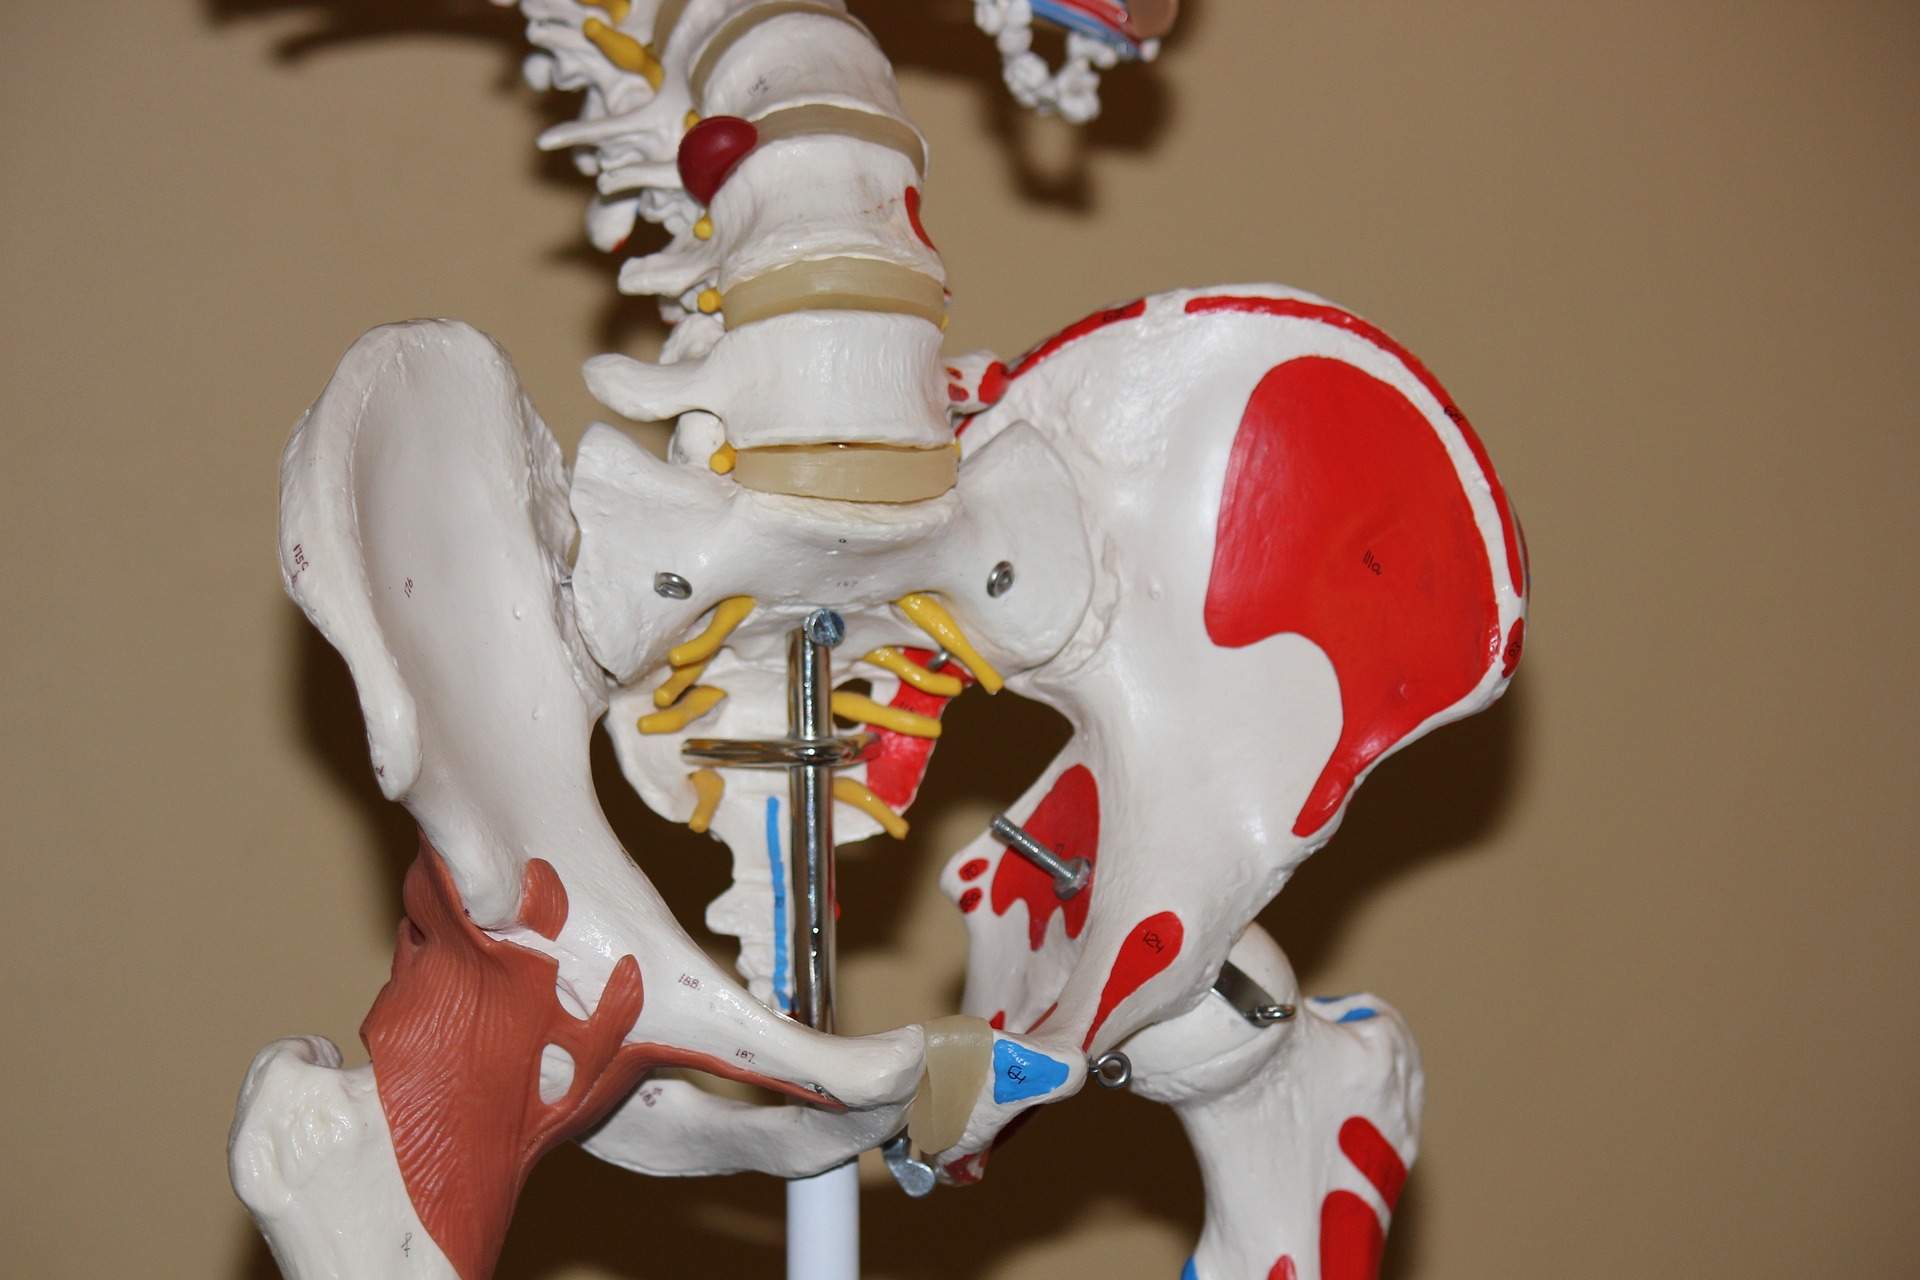

2. 관절염

대부분의 관절염 환자는 다리 또는 팔의 부위가 관절염에 가장 많이 호소합니다. 그러나 오른쪽 옆구리는 관절염이 있는 경우 아픈 경우가 생길 수 있습니다. 그 이유는 다음과 같습니다.

첫째, 오른쪽 옆구리는 다리보다는 가벼운 부위이기 때문에 오른쪽 옆구리의 관절이 스트레스를 받기 쉽게 됩니다. 관절염이 있는 경우 이러한 스트레스가 관절내에 쌓이게 되어 오른쪽 옆구리를 가려 아픔을 느낄 수 있게 됩니다.

둘째, 오른쪽 옆구리는 일상생활 중 운동을 잦게 하는 부위이기 때문에 관절염이 있는 경우 이 부위에 더 많은 스트레스를 줄 수 있기 때문에 오른쪽 옆구리가 아픈 경우가 발생합니다.

3. 허리디스크

대부분의 경우, 오른쪽 옆구리의 아픈 원인은 허리디스크에 의해 발생합니다. 허리디스크는 허리 관절과 뼈 사이의 연결부위, 즉 디스크가 상하로 압축되고 과다한 부하를 받아 탈락되는 것으로 이해되고 있습니다. 이는 외상성 손상 또는 척추관절의 노화에 의해 발생할 수도 있습니다. 허리디스크는 고령화가 진행됨에 따라 자주 발생하고, 일상생활에서 발생하는 많은 스트레스는 급성 허리디스크를 유발할 수 있습니다.

허리디스크가 약해지거나 탈락할 때, 그 주변의 뼈나 관절의 압박은 신경을 압박하거나 부실하게 만들 수 있으며, 이는 오른쪽 옆구리에 통증이나 불편감을 초래합니다. 또한, 허리디스크에 의해 신경이 압박되면 그 주변 근육이 긴장되고 근육해로 인한 추가 통증이 오른쪽 옆구리에 영향을 줄 수도 있습니다.